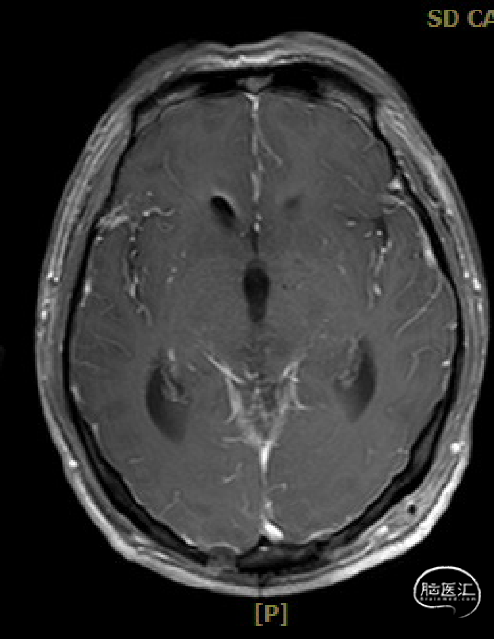

术前MRI与术后复查MRI对比